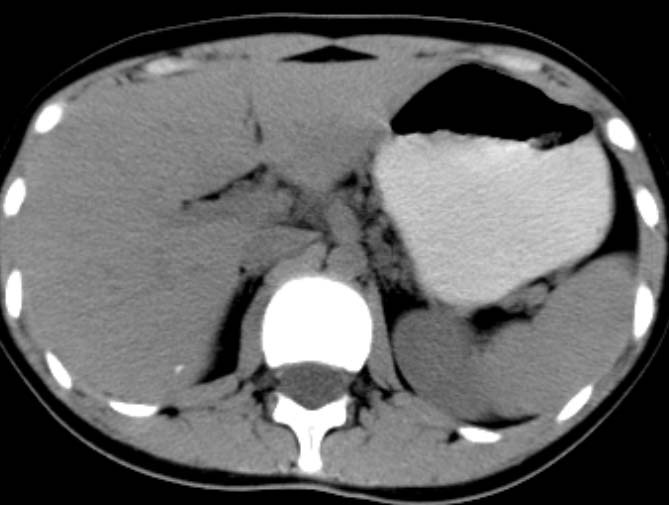

女,14岁。腹痛3天。腹部触诊未触及包块。碘剂阳性未增强。求助战友。。。。。。。。。。。

胰头部明显增大,胰管未见明显扩张,周围肠系膜血管显示清楚,胰头周围明显见渗出,还是考虑胰腺炎

胰头明显肿大呈肿物样,周围脂肪密度增高,结合病人年龄及临床表现,首先考虑炎性改变,建议结合实验室检查明确。必要是复查或mr检查

既然实验室检查不支持炎症,那就强化或mr检查帮助明确吧.

病灶应在胰头下区,不一定是胰头,结合周边低密度水肿,是否可能为十二指肠(xi)室炎症或其它炎症。

胰周无明显渗出,吉氏筋膜未见增厚。血尿试验室检查不支持。排除胰腺炎。